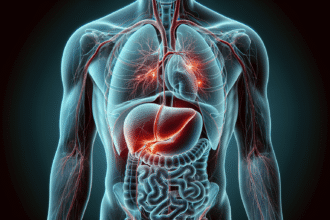

How Body Imaging Plays a Crucial Role in Diagnosing Gallbladder Issues

Gallbladder issues often begin with vague symptoms that can mimic other digestive concerns. Discomfort in the upper abdomen, nausea after…